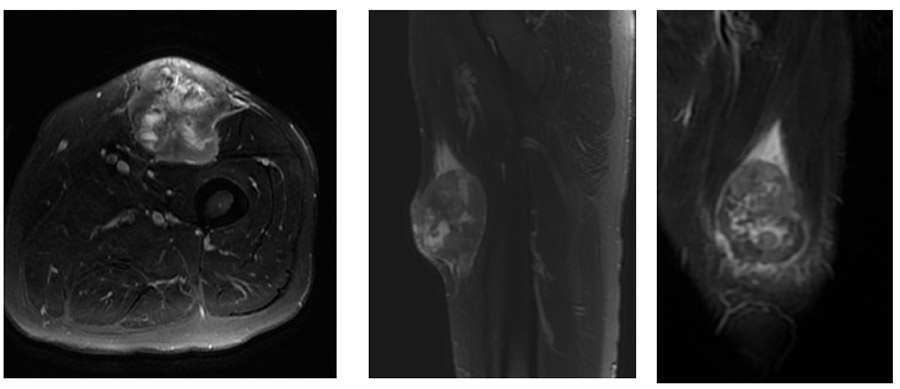

Ameliyat Öncesi: MR’da uyluk ön tarafta cildi invaze eden düzensiz sınırlı, periferik ödemin eşlik ettiği heterojen kitle görülmekte